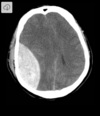

What type of herniation is depicted by the arrow? [1] Uncal Central (transtentorial) Cingulate (Subfalcine) Transcalvarial Upward cerebellar (transtentorial) Downward cerebellar (Tonsillar)

**Uncal** Central (transtentorial) Cingulate (Subfalcine) Transcalvarial Upward cerebellar (transtentorial) Downward cerebellar (Tonsillar)